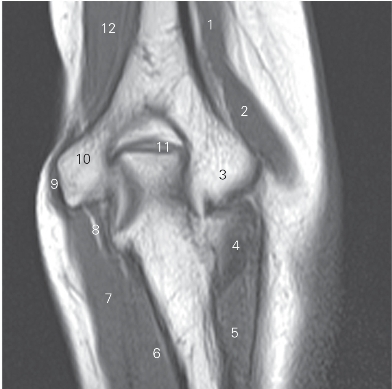

图4-35 经肘关节的冠状断层MR T1加权图像

1 肱二头肌 biceps brachii 2 桡侧腕长伸肌 extensor carpi radialis longus

3 肱骨小头 capitulum of humerus

4 肘肌 anconeus 5 尺侧腕伸肌 extensor carpi ulnaris

6 指深屈肌 flexor digitorum profundus

7 尺侧腕屈肌 flexor carpi ulnaris

8 尺神经 ulnar nerve 9 屈肌总腱 common flex tendon

10 内上髁 medial epicondyle

11 鹰嘴 olecranon 12 肱肌 brachialis